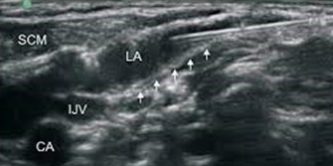

Come si può vedere dall’immagine che segue, con il blocco intermedio, facilmente l’anestetico diffonde verso la loggia vascolare anestetizzando i piani profondi e spesso il chirurgo riesce a completare l’intervento senza rinforzi.

Alcuni anestesisti procedono con l’ago verso i vasi e fanno un ulteriore infiltrazione perivascolare. Noi sconsigliamo tale manovra, in quanto aumenta il rischio di effetti collaterali come tachicardia da blocco del vago, difficoltà alla deglutizione da blocco del n. ipoglosso e riduzione del riflesso ipertensivo durante il clampaggio, fenomeno protettivo in questo tipo di procedura. E’ invece conveniente chiedere al chirurgo di infiltrare l’avventizia del vaso in particolare al livello del seno carotideo e nei punti in cui il paziente eventualmente riferisce fastidio.